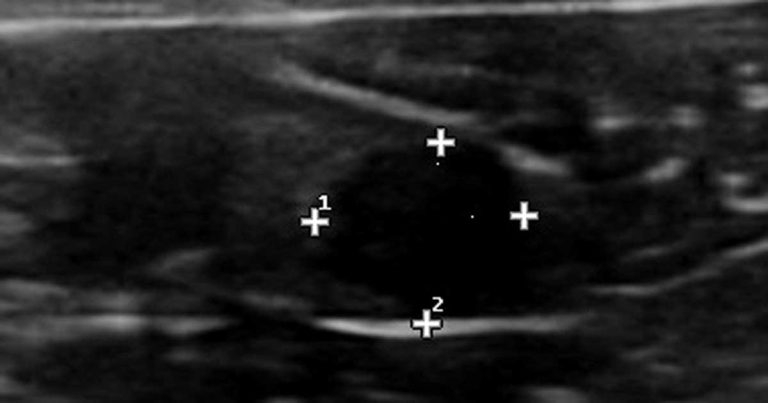

The only detected abnormalities were anechoic cysts in both ovaries. The biggest cyst was about 2cm in diameter. The pancreas and adrenal glands were within normal limits, and basal cortisol within reference range. Thyroid function was not assessed due to limited budget and absence of clinical signs. Ovariohysterectomy was performed, despite the uncontrolled DM.